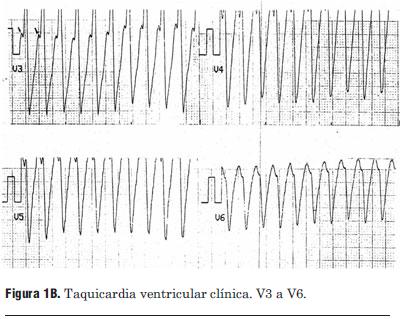

Paciente de 69 años de edad, sexo masculino, procedente del departamento de Tacuarembó. Ingresa al centro de tratamiento intensivo del Hospital de Tacuarembó el día 1º de febrero de 2010. Había consultado horas antes por episodio sincopal constatándose una taquicardia regular de complejos QRS anchos (figuras 1A y 1B), hipotensión arterial y mala perfusión periférica; es medicado inicialmente con adenosina intravenosa, sin respuesta; se resuelve cardiovertir eléctricamente; al administrar propofol i/v revierte espontáneamente a ritmo sinusal.

Figura 1B. Taquicardia ventricular clínica. V3 a V6.